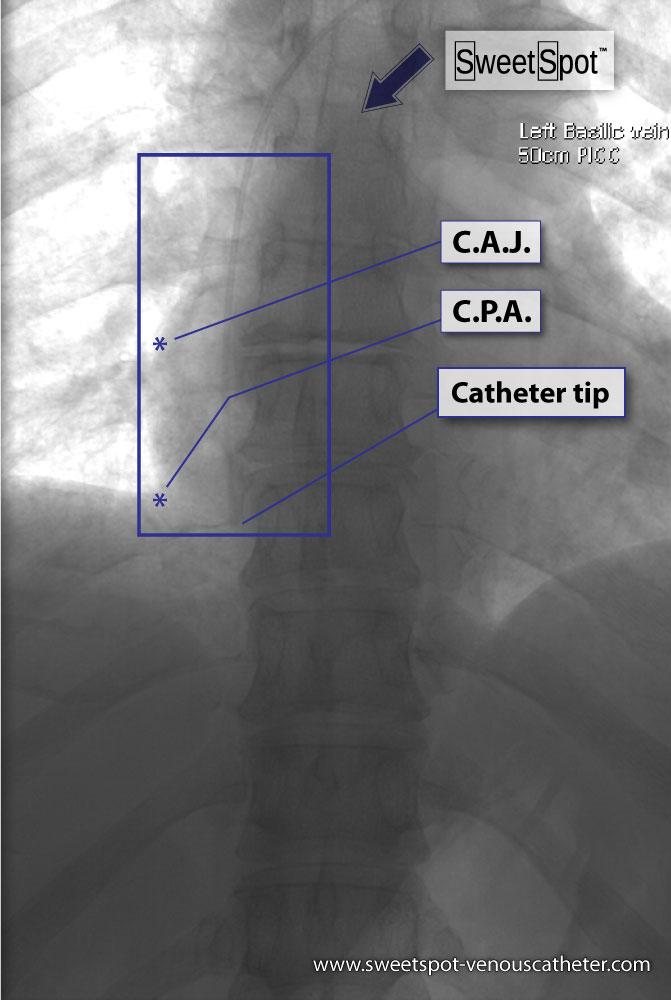

Figure - 22

Catheter Tip Position |